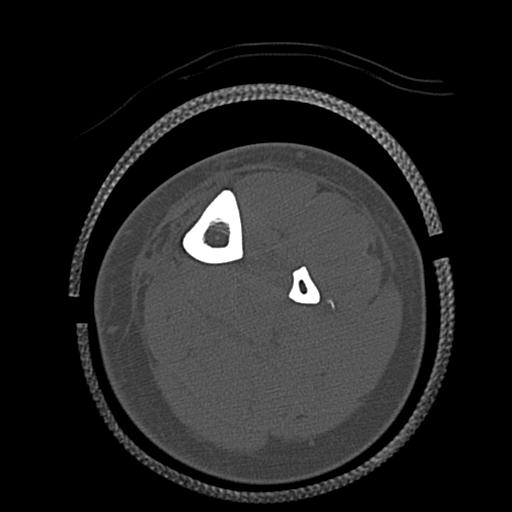

56476 8/28 4R 1/21 2R 左足関節 デジカメ写真 72歳女性 右足関節AS